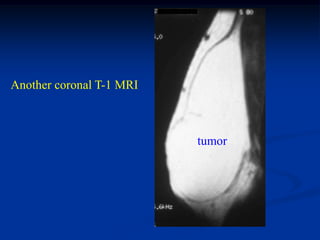

Case #1185

59 year female with

intramuscular lipoma

anterior proximal thigh

Coronal T-1 MRI

Axial T-2 MRI

at lower level

Fat subtraction MRI

showing signal void

in lipoma

Case #1185 59 yearfemale with intramuscular lipoma anterior proximal thigh Coronal T-1 MRI

• 54.

• 55.

Axial T-2 MRI atlower level

• 56.

Fat subtraction MRI showingsignal void in lipoma